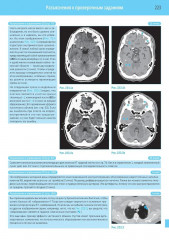

💳 Оплатить за товар можно при получении 🇰🇿 Есть бесплатная доставка по Казахстану от 1 дня 🎁 Копите бонусы с каждой покупки Четвертое издание на русском языке представляет собой базовый курс подготовки и переподготовки специалистов по компьютерной томографии по международным стандартам. Представлен систематизированный подход к анализу компьютерных томограмм всех частей тела. Описаны самые современные методики, включая КТ-ангиографию, КТ с двумя источниками и ПЭТ/КТ. Книга содержит более 1000 высококачественных иллюстраций — компьютерных томограмм со схемами, иллюстрирующими их анатомический смысл и диагностическое значение. Каждая глава содержит задания для самоконтроля, что позволяет читателю самостоятельно организовать и контролировать процесс обучения. |